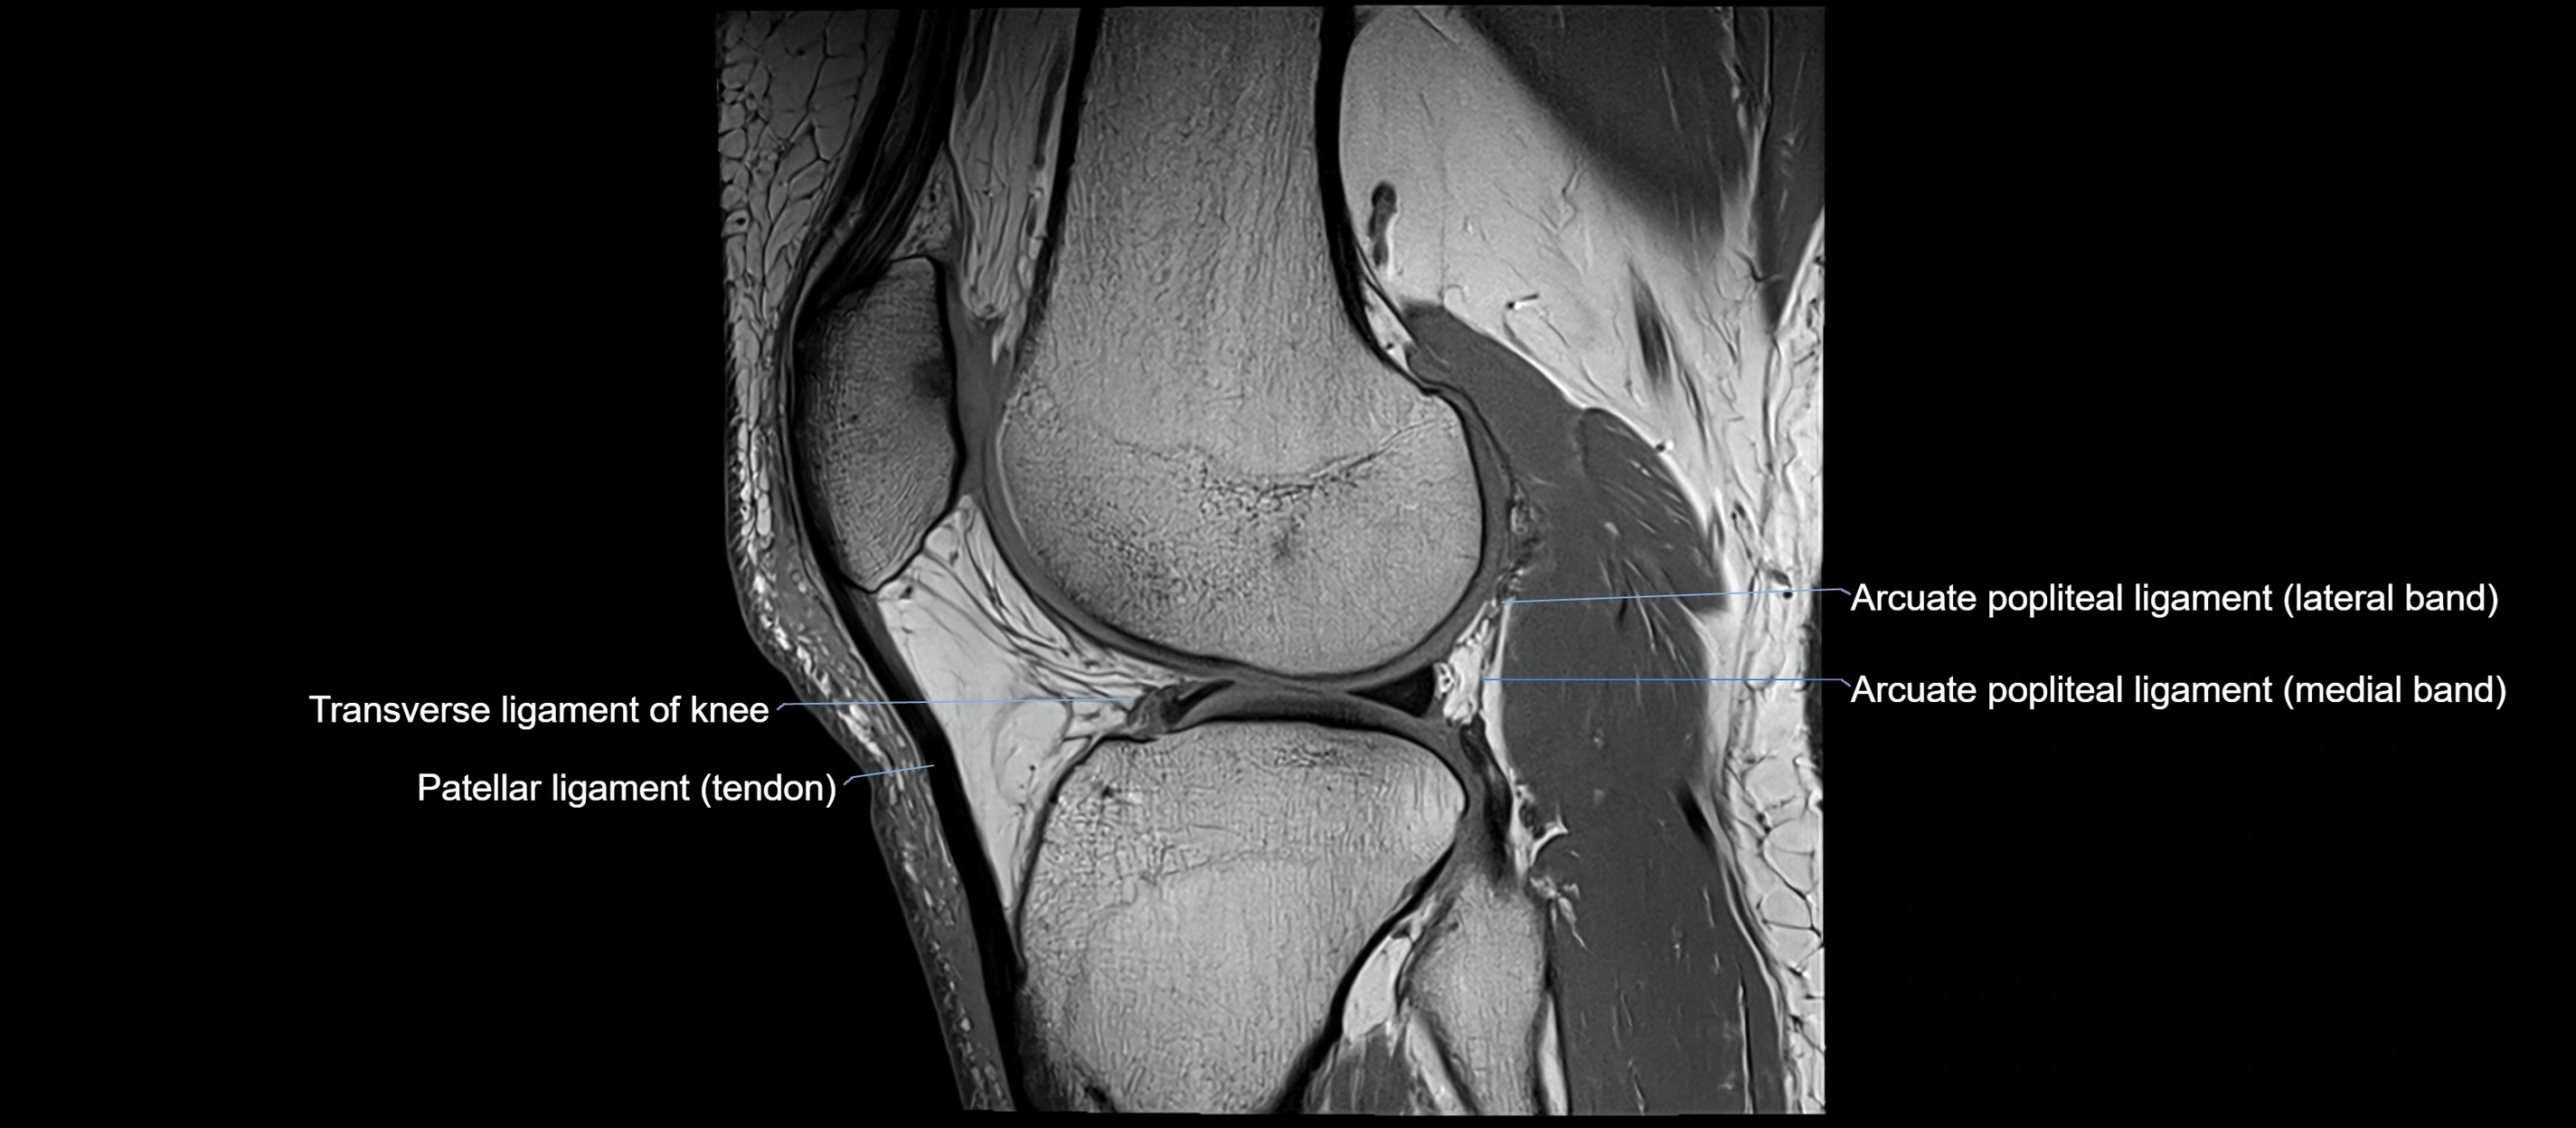

The anterior cruciate ligament (ACL) is one of the major stabilizing ligaments of the knee. It lies within the joint capsule but outside the synovial cavity. The ACL extends obliquely through the intercondylar notch, connecting the tibia to the femur, and resists anterior translation of the tibia relative to the femur. It is crucial for maintaining stability during pivoting, cutting, and deceleration movements, making it one of the most frequently injured structures in sports.

Origin and Insertion

• Origin:

• Arises from the anterior intercondylar area of the tibia, just medial to the tibial spine

• Course:

• Passes superiorly, posteriorly, and laterally through the intercondylar notch of the femur

• Lies anterior to the posterior cruciate ligament (PCL) and crosses it obliquely, forming the cruciate arrangement

• Insertion:

• Attaches to the posterior aspect of the medial surface of the lateral femoral condyle within the intercondylar fossa

MRI Appearance

T1-weighted images:

• Normal ACL appears as a low-signal band-like structure crossing the intercondylar notch

• Surrounded by intermediate signal synovial fluid and fat planes

T2-weighted images:

• Normal ACL remains low signal

• Partial or complete tears appear as discontinuity, increased signal, or fiber laxity

MRI images

image